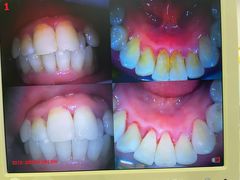

• 新达口腔(华东理工大学店)

• -新达口腔(华东理工大学店)